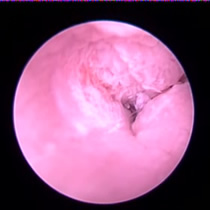

角化症、脂漏症という生まれつきの体質を持ったワンちゃんは耳垢が多くなりがちです。また、角化症、脂漏症の長毛種となれば、耳の中に毛が生えた犬種も多く耳道から耳垢を排泄しにくくなります。それらが原因で耳に汚れがたまります。また長毛種はトリミングに行く回数も多く、耳を洗う機会が多くなります。こんな負の連鎖があり、いずれも耳を悪くする大きな原因になります。その全ての要因に対処しなければ耳の病気は解決しません。写真は鼓膜手前に耳垢や毛が蓄積し、通常の耳洗浄ではきれいにできない状態です。セカンドオピニオンで来院されるワンちゃんで最も多い病気の1つです。

フレンチブルドックはアトピー性皮膚炎、食物アレルギー、脂漏症、甲状腺機能低下症など皮膚病になりやすい犬種です。さらにフレンチブルドックの耳道はもともと入口がとても広く、鼓膜手前で極端に狭くなっています。もし、これらの皮膚病を発症すると外耳炎が起こりやすくなります。外耳炎が起こると耳垢が溜まり、耳洗浄による耳道刺激があったり、微生物の増殖など負のサイクルに陥ることがあります。さらに耳道周囲の体毛が耳の中に入りやすいため、鼓膜手前に毛が蓄積します(写真)。体毛、微生物が増殖した耳垢、皮膚病の放置といった悪化因子が重なると非常に重度の中耳炎になります。